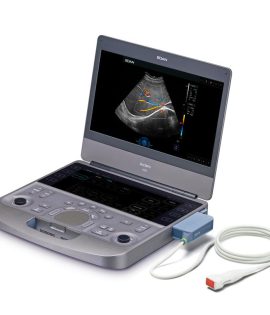

Ecógrafo Estacionario EDAN Acclarix LX25

Ecógrafo Estacionario EDAN Acclarix LX25

- Monitor LCD de 21.5″ HD con ángulo de visión multidimensional.

- Pantalla táctil de alta sensibilidad de 14″ que permite un funcionamiento eficaz.

- Diseño de calentador de gel.

- Configuración de 3 puertos para transductores.

- Diseño de ajuste de altura ergonómico.

- Baterías de respaldo y tiempo 2h de exploración continua.

- eOptimized – Una optimización clave en B/Color/PW.

- PW auto trace – Una tecla en la medición automática.

- eTouch – Eficiente control gestual Swipe.

- eLearn – Software tutorial de fácil uso.

- Conectividad DICOM 3.0.

Gracias a la innovadora tecnologia EDAN TAI, ya las múltiples tecnologías de procesamiento de

imágenes, Acclarix LX25 puede mostrar perfectamente la imágen de ultrasonido en diferentes

modos. ayudando al ecografista a realizar un diagnostico más preciso

La arquitectura de alta fidelidad y alto número de canales da como resultado una magnífica resolución

de los detalles, especialmente en profundidad.

Tissue Adaptive Imaging (TAI) optimiza de forma continua y automática las imágenes, lo que permite

centrarse más en el paciente.

En modo B, el TAI ajusta múltiples parámetros para proporcionar la mejor calidad de imagen posible.

En el Doppler, el TAI se ajusta automáticamente al estado del flujo, proporcionando una mejor continuidad,

detección de bordes y llenado de color.

Almacenamiento en disco duro SSD de 512GB

| Peso | 55 kg |

| Dimensiones | 66 × 54 × 144 cm |